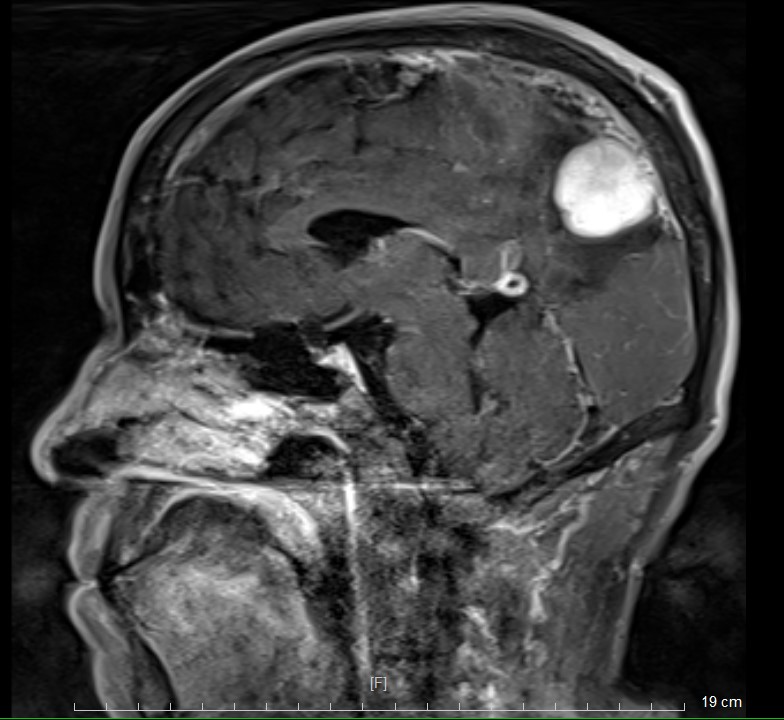

头部MR检查提示:左顶枕镰旁脑膜瘤

术后MR复查提示肿瘤切除干净